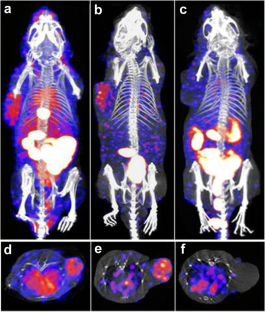

[99mTc]HYNIC-PEG11-Tz was successfully radiosynthesized with a specific activity of 9.25 MBq/μg and a radiochemical purity above 95 % as confirmed by reversed-phase HPLC (RP-HPLC). [99mTc]HYNIC-PEG11-Tz showed favorable stability in NS, PBS, and FBS and rapid blood clearance in mice. The atezolizumab was modified with TCO-NHS ester to produce a conjugate with an average 6.4 TCO moieties as confirmed by liquid chromatograph-mass spectrometer (LC-MS). Size exclusion HPLC revealed almost complete reaction between atezolizumab-TCO and [99mTc]HYNIC-PEG11-Tz in vitro, with the 1:1 Tz-to-mAb reaction providing a conversion yield of 88.65 ± 1.22 %. Pretargeted cell immunoreactivity binding and saturation binding assays showed high affinity to H1975 cells. After allowing 48 h for accumulation of atezolizumab-TCO in H1975 tumor, pretargeted in vivo biodistribution revealed high uptake of the radiotracer in the tumor with a tumor-to-muscle ratio of 27.51 and tumor-to-blood ratio of 1.91. Pretargeted SPECT imaging delineated the H1975 tumor clearly. Pretargeted biodistribution and SPECT imaging in control groups demonstrated a significantly reduced tracer accumulation in the A549 tumor.